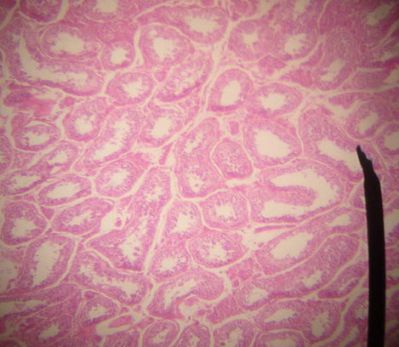

Testes - histology slide

This is a histology slide of the testes.

Original image by Jpogi at Wikipedia, via Wikimedia Commons. Public domain.

Changes were made to the original image.